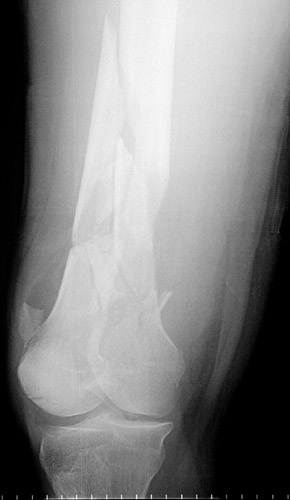

This radiograph reveals a

highly comminuted

spiral fracture of the distal femur with

displacement of bone fragments

. This was the result of a high speed vehicular accident.